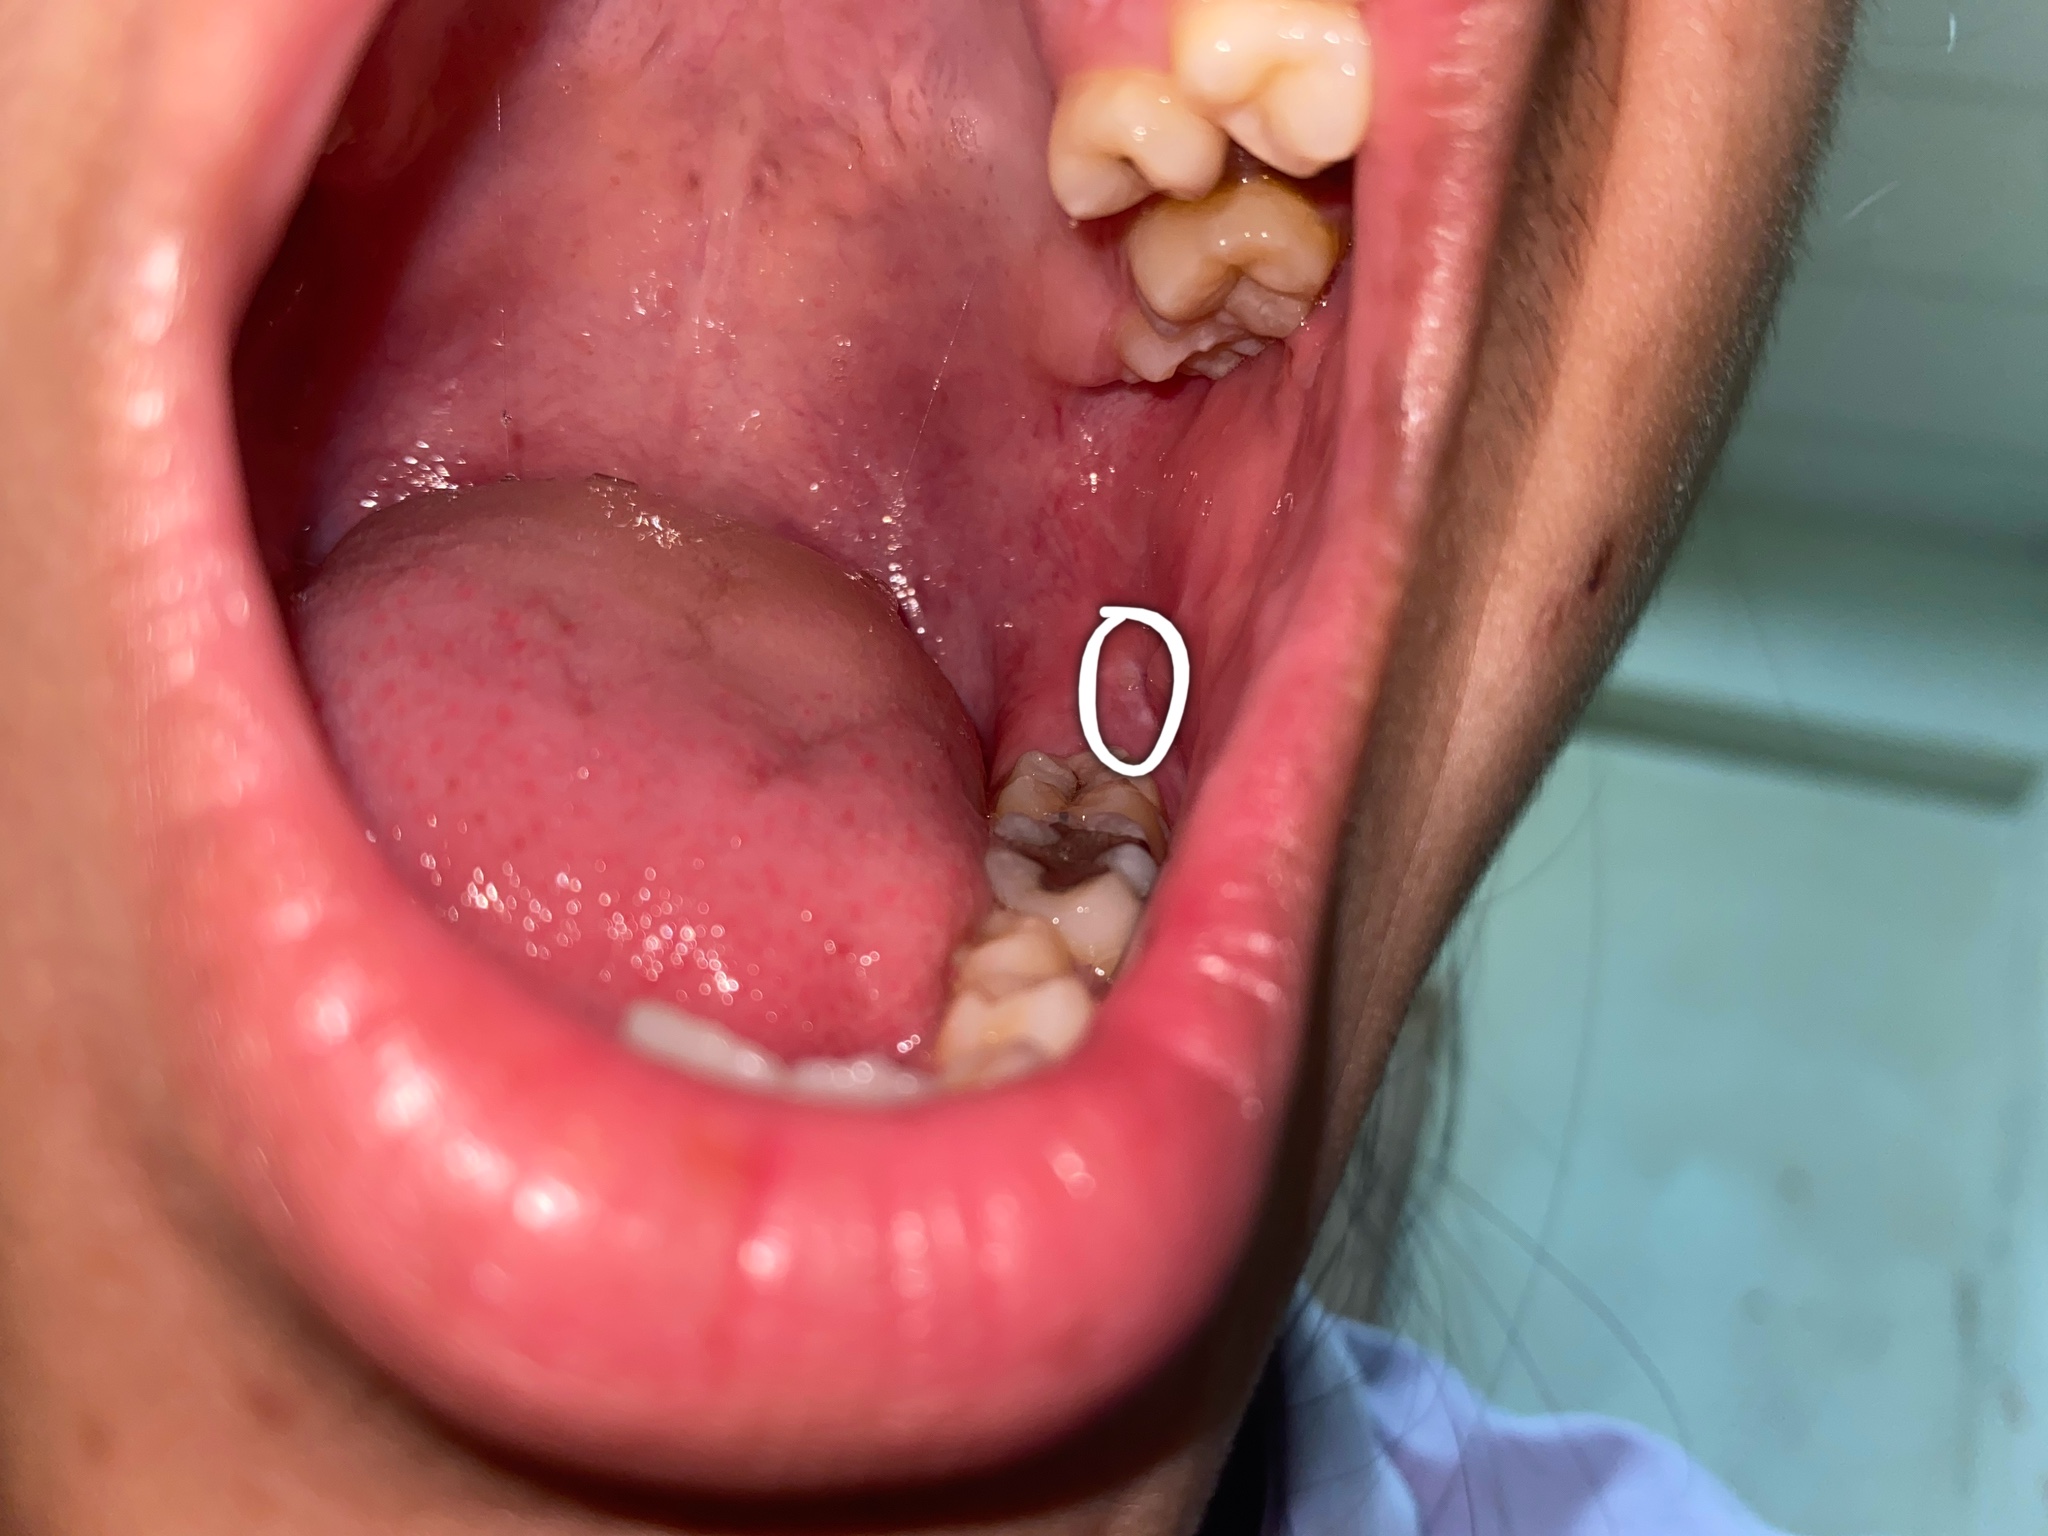

มีตุ่มสีขาวๆ อยู่ในปากต้องรักษายังไงคะ